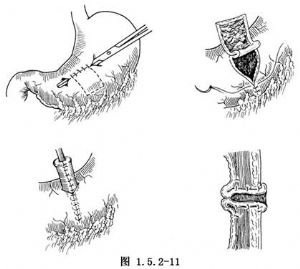

设计胃壁瓣的部位与管式胃造口术相同,只是将瓣的基底部放在胃小弯侧。在胃壁预定的基底部横放一把血管钳,用不吸收线沿血管钳两侧将胃前壁浆肌层做间断缝合,使胃壁突入胃腔内形成脊状,缝成管状后即成为一个活瓣(图1.5.2-11)。